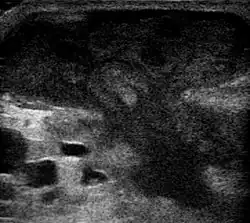

| Diagnostic method | Ultrasound, CT scan[1][3] |

They are usually caused by a bacterial infection.[10] Often many different types of bacteria are involved in a single infection.[8] In many areas of the world, the most common bacteria present are methicillin-resistant Staphylococcus aureus.[1] Skin abscesses in particular are overwhelmingly caused by S. aureus.[11] Rarely, parasites can cause abscesses; this is more common in the developing world.[3] Diagnosis of a skin abscess is usually made based on what it looks like and is confirmed by cutting it open.[1] Ultrasound imaging may be useful in cases in which the diagnosis is not clear.[1] In abscesses around the anus, computer tomography (CT) may be important to look for deeper infection.[3]

An abscess is a localized collection of pus (purulent inflammatory tissue) caused by suppuration buried in a tissue, an organ, or a confined space, lined by the pyogenic membrane.[31] Ultrasound imaging can help in a diagnosis.[32]